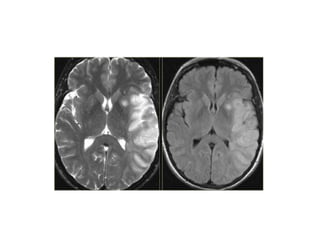

• On T2WI and FLAIR infarction is seen as

high SI.

These sequences detect 80% of

infarctions before 24 hours.

They may be negative up to 2-4 hours

post-ictus!

• High signal on conventional MR-

sequences is comparable to hypodensity

on CT.

It is the result of irreversible injury with cell

death.

So hyperintensity means BAD news: dead

brain.